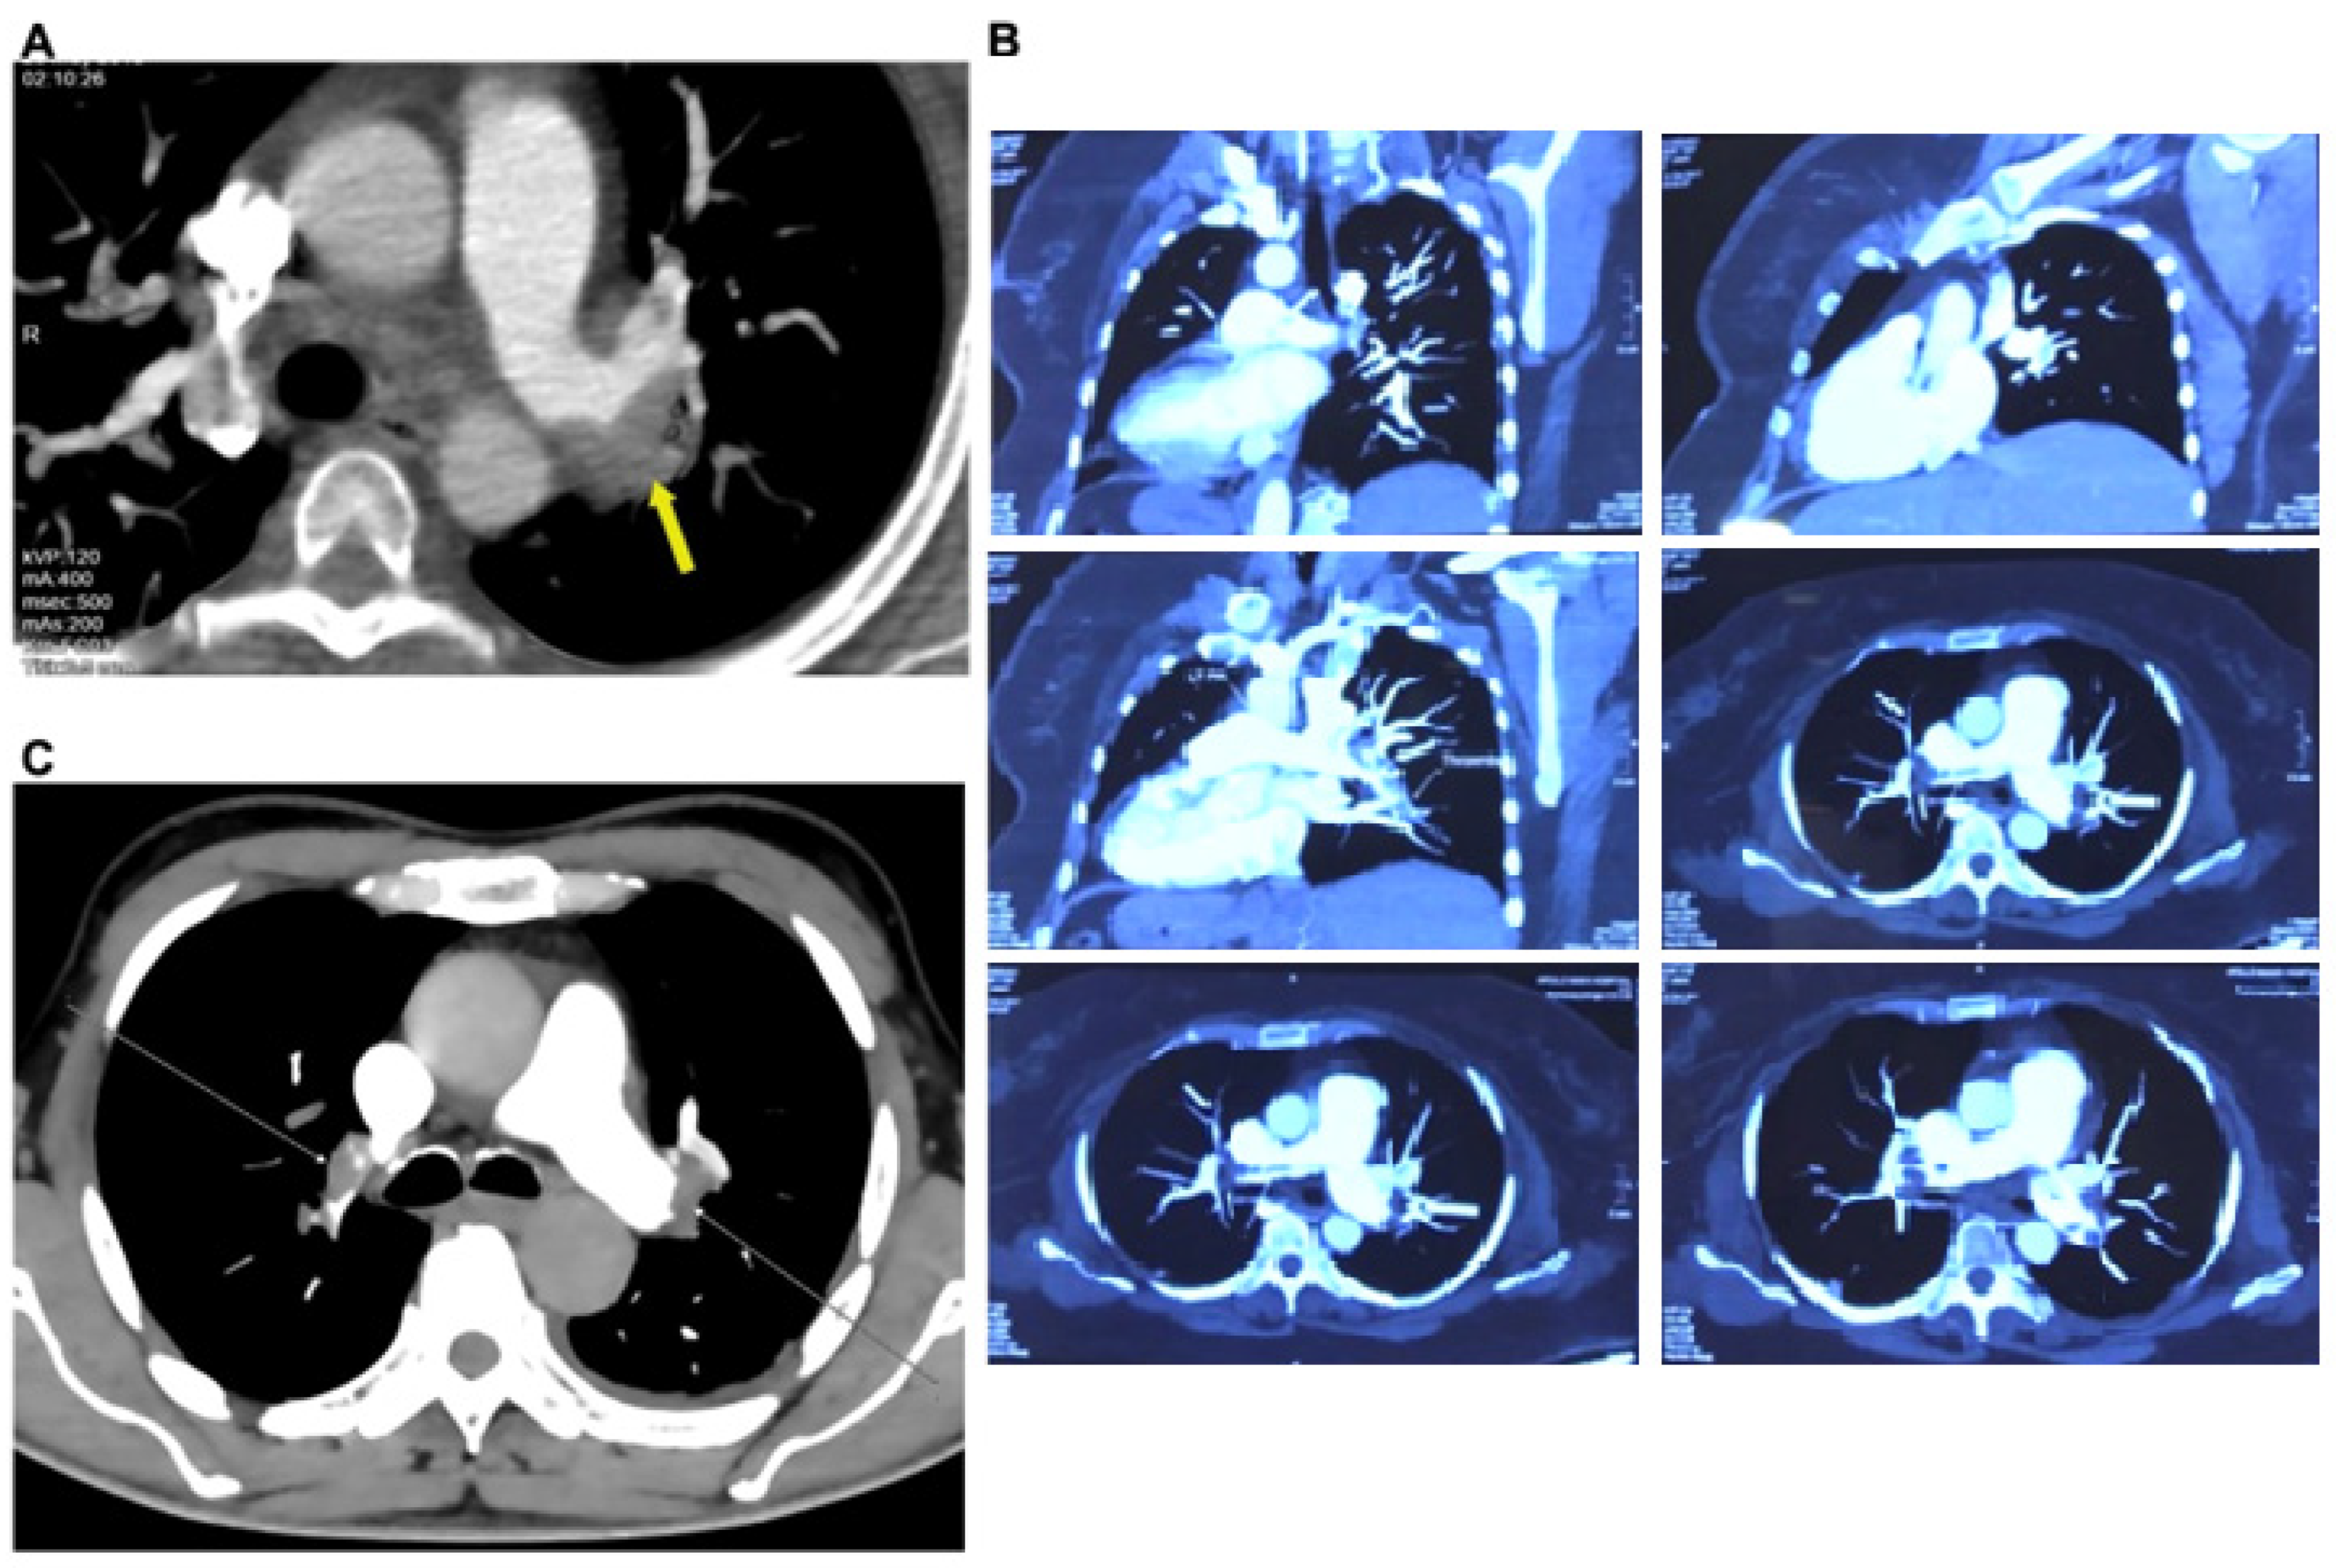

2.2. Cardiogram Methods and CT Pulmonary Angiogram Confirmed Pulmonary Embolism

5.5. CT Pulmonary Angiogram